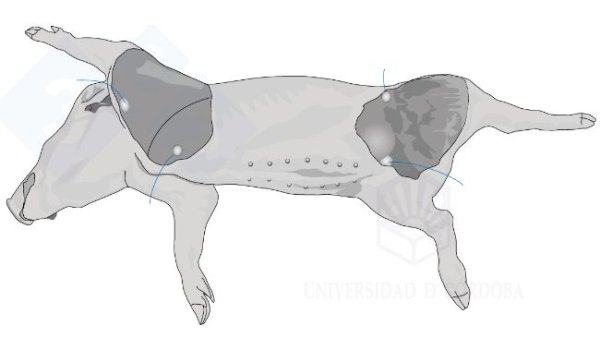

In dieser neuen Rubrik, die vom Team für pathologische Anatomie der Universität Córdoba (Spanien) betreut wird, werden wir Schritt für Schritt und auf sehr anschauliche und praktische Weise zeigen, wie eine Nekropsie an einem Schwein durchgeführt wird.

In den ersten beiden Kapiteln haben wir uns mit der Nekropsie in seitlicher Dekubitus-Lage befasst. In diesem dritten Kapitel behandeln wir die Nekropsie in Rückenlage.